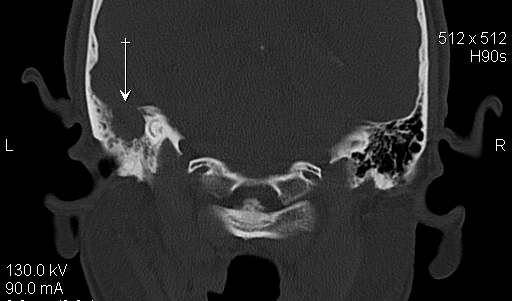

JFC Sinusitis maxilar. Espolón septal.